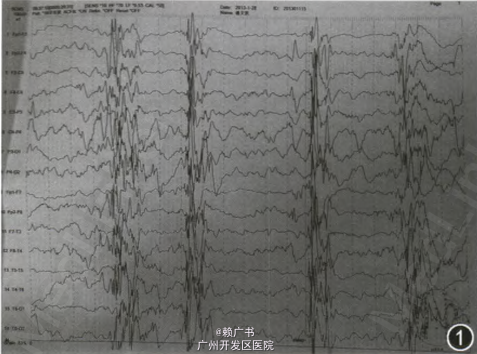

视频脑电图:广泛性低 - 高波幅不同步不对称棘波、尖波、棘 - 慢节律,清醒及睡眠期同时存在(爆发性活动与抑制状态交替出现)。